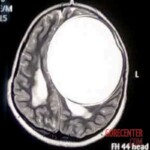

Her parents tried to get medical help, but none of the doctors they visited were sufficiently educated in neurology. Finally, they came across Dr. Chirag Solanki, who performed an MRI on the girl and made a horrifying finding – there was a giant cyst in the girl’s skull.

The cyst was said to have been growing for 8-10 years. It weighed a whopping 675 grams. If it had burst, the girl would have died instantly. But the cyst was successfully removed by surgery.